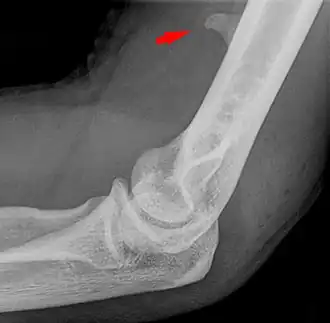

Small supracondylar process seen on a lateral radiograph of the elbow

The supracondylar process of the humerus (also known as an avian spur) is a variant bony projection on the anteromedial aspect of the upper arm bone (humerus), about 5–6 cm above the medial epicondyle.[1] It is directed downward, forward and medially pointing to the medial epicondyle. A fibrous band, Struthers ligament, may connect this process to the medial epicondyle.[2] This variation has a prevalence of 0.68% and is significantly more common in women than in men.[3]